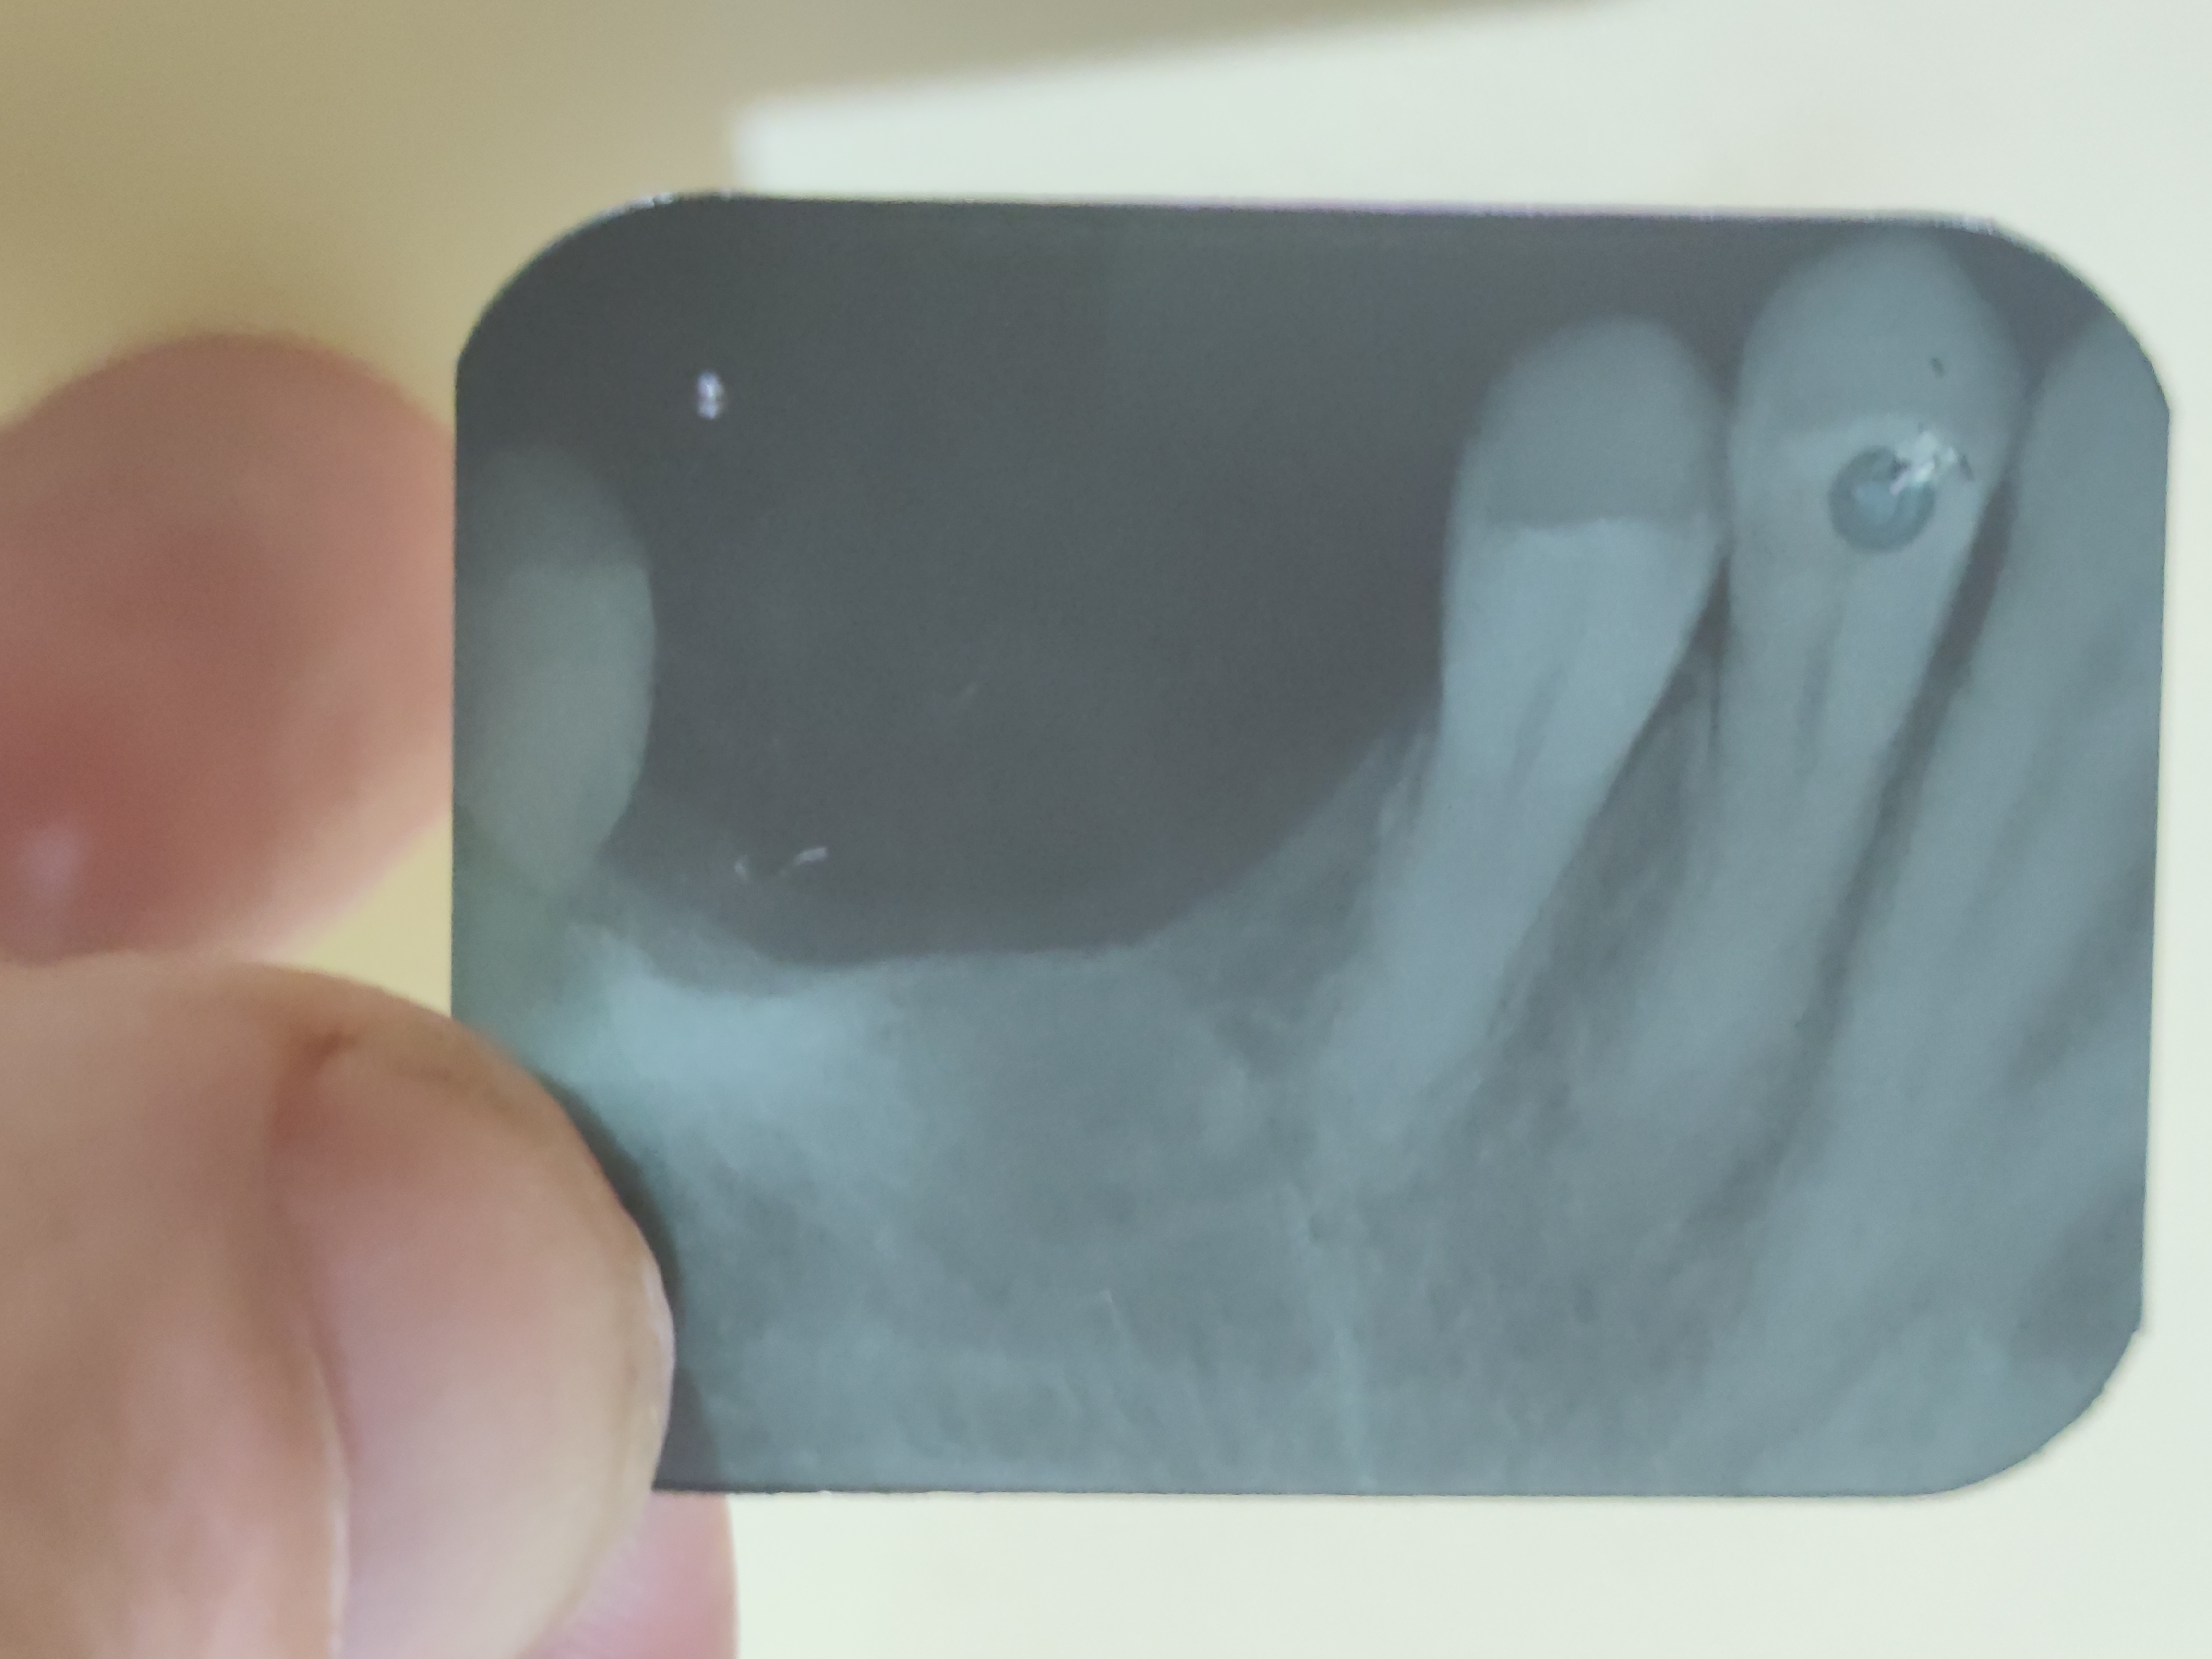

this is left upper 4 and 5, then a large gap where

molar 1 and 2 (LU5/LU6) were extracted after

rotting so badly the left side of my jaw bone is

entirely missing.

the dental report confirms peridontitis has

affected both LU4 and LU5.

combined with the brain CT Scan report

of left lower (maximillary) sinus being

"polypoid" it confirms a chronic infection,

again supported by the blood tests of IL-6 38.8

3dec25

the left lower sinus is right next to where the

failed root canal was.